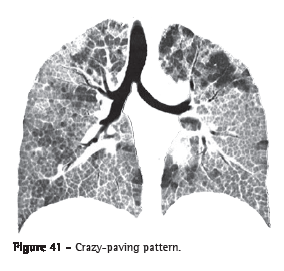

Crazy-paving pattern (padrão de pavimentação em mosaico)

The crazy-paving pattern presents superimposition of ground-glass

opacities, interlobular lines and thickened interlobular septa (Figure 41).

The interface between the normal and the affected lungs tends to be well-delimited in this pattern of pulmonary lesion. This pattern was initially identified in patients with pulmonary alveolar proteinosis, but it can also be seen in other diffuse pulmonary diseases in which the interstitial and alveolar compartments are affected (e.g., pulmonary hemorrhage).(1,2,64)